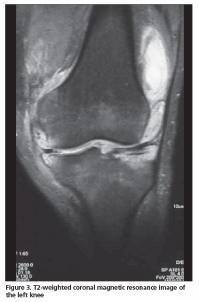

A 72-year-old male patient was admitted to our outpatient clinic with pain, swelling, and limited range of motion of the left knee, and difficulty in walking. His knee complaints had begun suddenly 1 year ago and he also had intermittent right hip joint pain. He had 1 hour of morning stiffness and his symptoms were slightly reduced by activity. He did not have any episodes of infections prior to symptom onset. He did not report fever, weight loss or sweating, and his rheumatologic history was uneventful other than his joint complaints. Despite the use of several non-steroidal anti-inflammatory drugs, there was no improvement in his knee pain, swelling, and range of motion. The anamnesis of the patient was unremarkable except he was treated for pulmonary TB 50 years ago and underwent surgery on his right hip due to trochanteric bursitis 3 years ago. On physical examination swelling and limited range of motion was observed in left knee. After activity, pain and increased temperature was also noted. His right hip joint motion was mildly painful without any limitation. Laboratory investigations revealed a white blood cell count of 6200/uL (normal range; 4800-10800/uL), hemoglobulin level of 12.8 mg/dL (normal range; 12-17 mg/dL), platelet count of 630.000/uL, erythrocyte sedimentation rate of 59 mm/h (normal range; 0-20 mm/h), blood glucose level of 110 mg/dL (normal range; 70-110 mg/dL), a C-reactive protein level of 8.99 mg/dL (normal value; <0.3 mg/dL), RF level of 63.70 IU/mL (normal value; <19 IU/mL), and anti-CCP antibody as 21.8 U/mL (normal value; 0-5 U/mL). The synovial fluid examination revealed a white blood cell count of 16.200/uL and a blood glucose level of 12 mg/dL. Marginal erosions were noted on the radiograph of the left knee (Figure 1). The anteroposterior pelvic radiograph revealed a region of ossification lateral to the right hip joint corresponding to the trochanteric bursa region. Magnetic resonance imaging (MRI) of the left knee revealed extensive hyperintense synovial thickening and erosive changes within the joint cavity, including all knee compartments and the suprapatellar bursa on T2-weighted images (Figures 2, 3). On contrast-enhanced MRI evaluation, fields of necrosis associated with infection showing peripheral enhancement were observed. Bone and joint pathologies defined in these investigations were compatible with infection. The differential diagnosis included arthritis, osteomyelitis, and especially TB, thus the Departments of Infectious Diseases, Chest Diseases, and Orthopedics were consulted. The Department of Infectious Diseases recommended that two consecutive joint aspiration samples should be screened for acid-resistant bacilli (ARB). Indeed, ARB were detected in both joint aspiration fluid samples. On lung tomography, as recommended by the Department of Chest Diseases, revealed fibrotic scars in the bilateral upper lobes, which were thought to be secondary to previous infection. Arthroscopic debridement was performed by the Department of Orthopedics and the biopsy result was compatible with a granulomatous inflammatory reaction. The patient was diagnosed with TB arthritis and treated accordingly. Clinical and laboratory improvement was noted on follow-up.